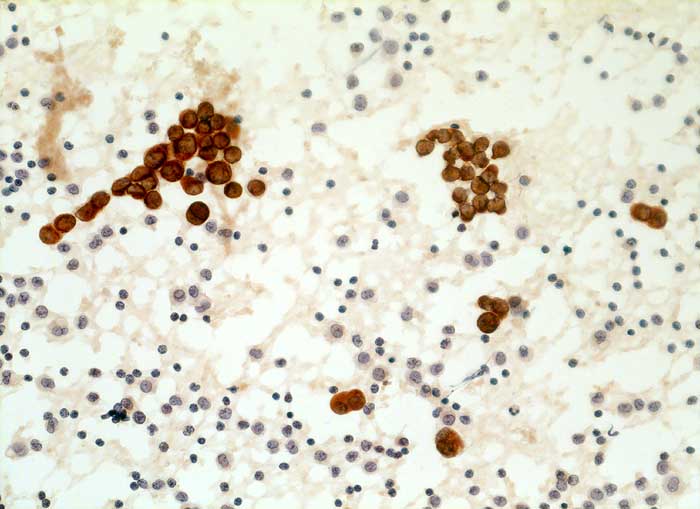

Aszitespunktat: Die Mesothelzellen sind positiv für den Panzytokeratinmarker Lu-5. Die Entzündungszellen sind Lu-5 negativ.

Immunzytochemisch reagieren erwartungsgemäss die Mesothelien deutlich mit dem panepithelialen Antikörper Lu-5. Mit dem epithelialen Marker Ber-EP4 stellen sich jedoch keine Zellen dar. Dies spricht gegen das Vorliegen eines Karzinoms.

Zytologische Diagnose: Keine Malignität

Kommentar: Leicht abnorme Mesothelverbände oder Makrophagenaggregate sind typisch für Ergüsse bei Lebererkrankung. Die Differentialdiangose gegenüber einem Karzinom ist manchmal schwierig. Da BerEp-4 in ca. 90% aller Karzinome positiv ist, Mesothelien aber nicht mit dem Marker reagieren, ist dieser Marker eine wertvolle Hilfe. Die Mesothelzellverbände sind dagegen für Lu-5 und polyklonales Keratin positiv und nicht zur Differenzierung von Mesothelien und Karzinomzellen geeignet.

Lu5 Panzytokeratin

200